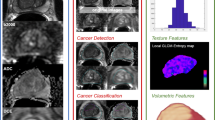

Compared with traditional medical imaging, radiomics has the strong ability of extracting more critical and comprehensive information of lesions with high throughput by quantitative methods [19,20,21]. It enables automatic localization and characterization of PCa as well as identifies the great value of grading and staging, therapeutic evaluation, prognostic analysis, and even genomics, helping a lot in clinical diagnosis and treatment decisions. Hence, this article reviews the basic concepts of radiomics and its current state-of-the-art in PCa.

Radiomics is a multi-disciplinary technology, of which the core steps include data acquisition, features selection, model building, and analysis, aiming at converting routine clinical images into mineable data, with high fidelity and high throughput.

The process of radiomics generally consists of several closely related steps as followed:

Feature extraction and quantification

Extraction and quantification of the imaging features which could characterize the attributes of the target area are the heart of radiomics. There are two types of features extracted in radiomics: “semantic” and “agnostic” features [24]. The former “semantic” is used to describe qualitative morphological features such as size, shape, location, vascularity, speculation, necrosis, and attachments or lepidics. The latter “agnostic” refers to invisibly quantitative description of heterogeneity of lesions such as textures, histogram, wavelets, Laplacian transforms, Minkowski functionals, and fractal dimensions. Textures can be obtained through first-, second-, and high-order statistical methods generally. The first-order features based on histogram mainly include maximum, minimum, average, standard deviation, variance, energy, entropy, sharpness, skewness, and kurtosis, gray-scale, which acquire relevant statistical information by frequency distribution of different gray levels in ROI. Second-order texture feature algorithms include gray-level co-occurrence matrix (GLCM) [35] and gray-level run-length matrix (GLRLM) [36]. High-order algorithms customarily make use of neighborhood gray-tone difference matrix (NGTDM) [37] and gray-level size zone matrix (GLSZM) [38]. As for methods based on models or transformation, Laplacian transforms are often utilized in image preprocessing and wavelet transform is in extracting texture features from sub-images to mine information more deeply. Similarly, a lot of software packages have been put into features extraction such as IBEX [39], MaZda [40], Pyradiomics [41], CERR [42], ePAD [43], LifeX [44], and some other R-based or MATLAB-based programs. Cooperative use of different software may help to acquire more comprehensive radiomics features.

In PCa, radiomics has been intensively applied to tumor detection, localization, staging, aggressiveness assessment, treatment decision-making assistant, and patient follow-up.